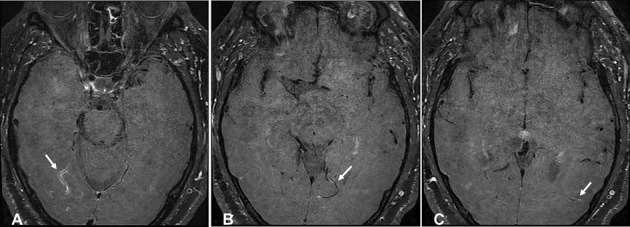

Clinical Images: High-resolution vessel wall magnetic resonance imaging detecting central nervous system vasculitis.